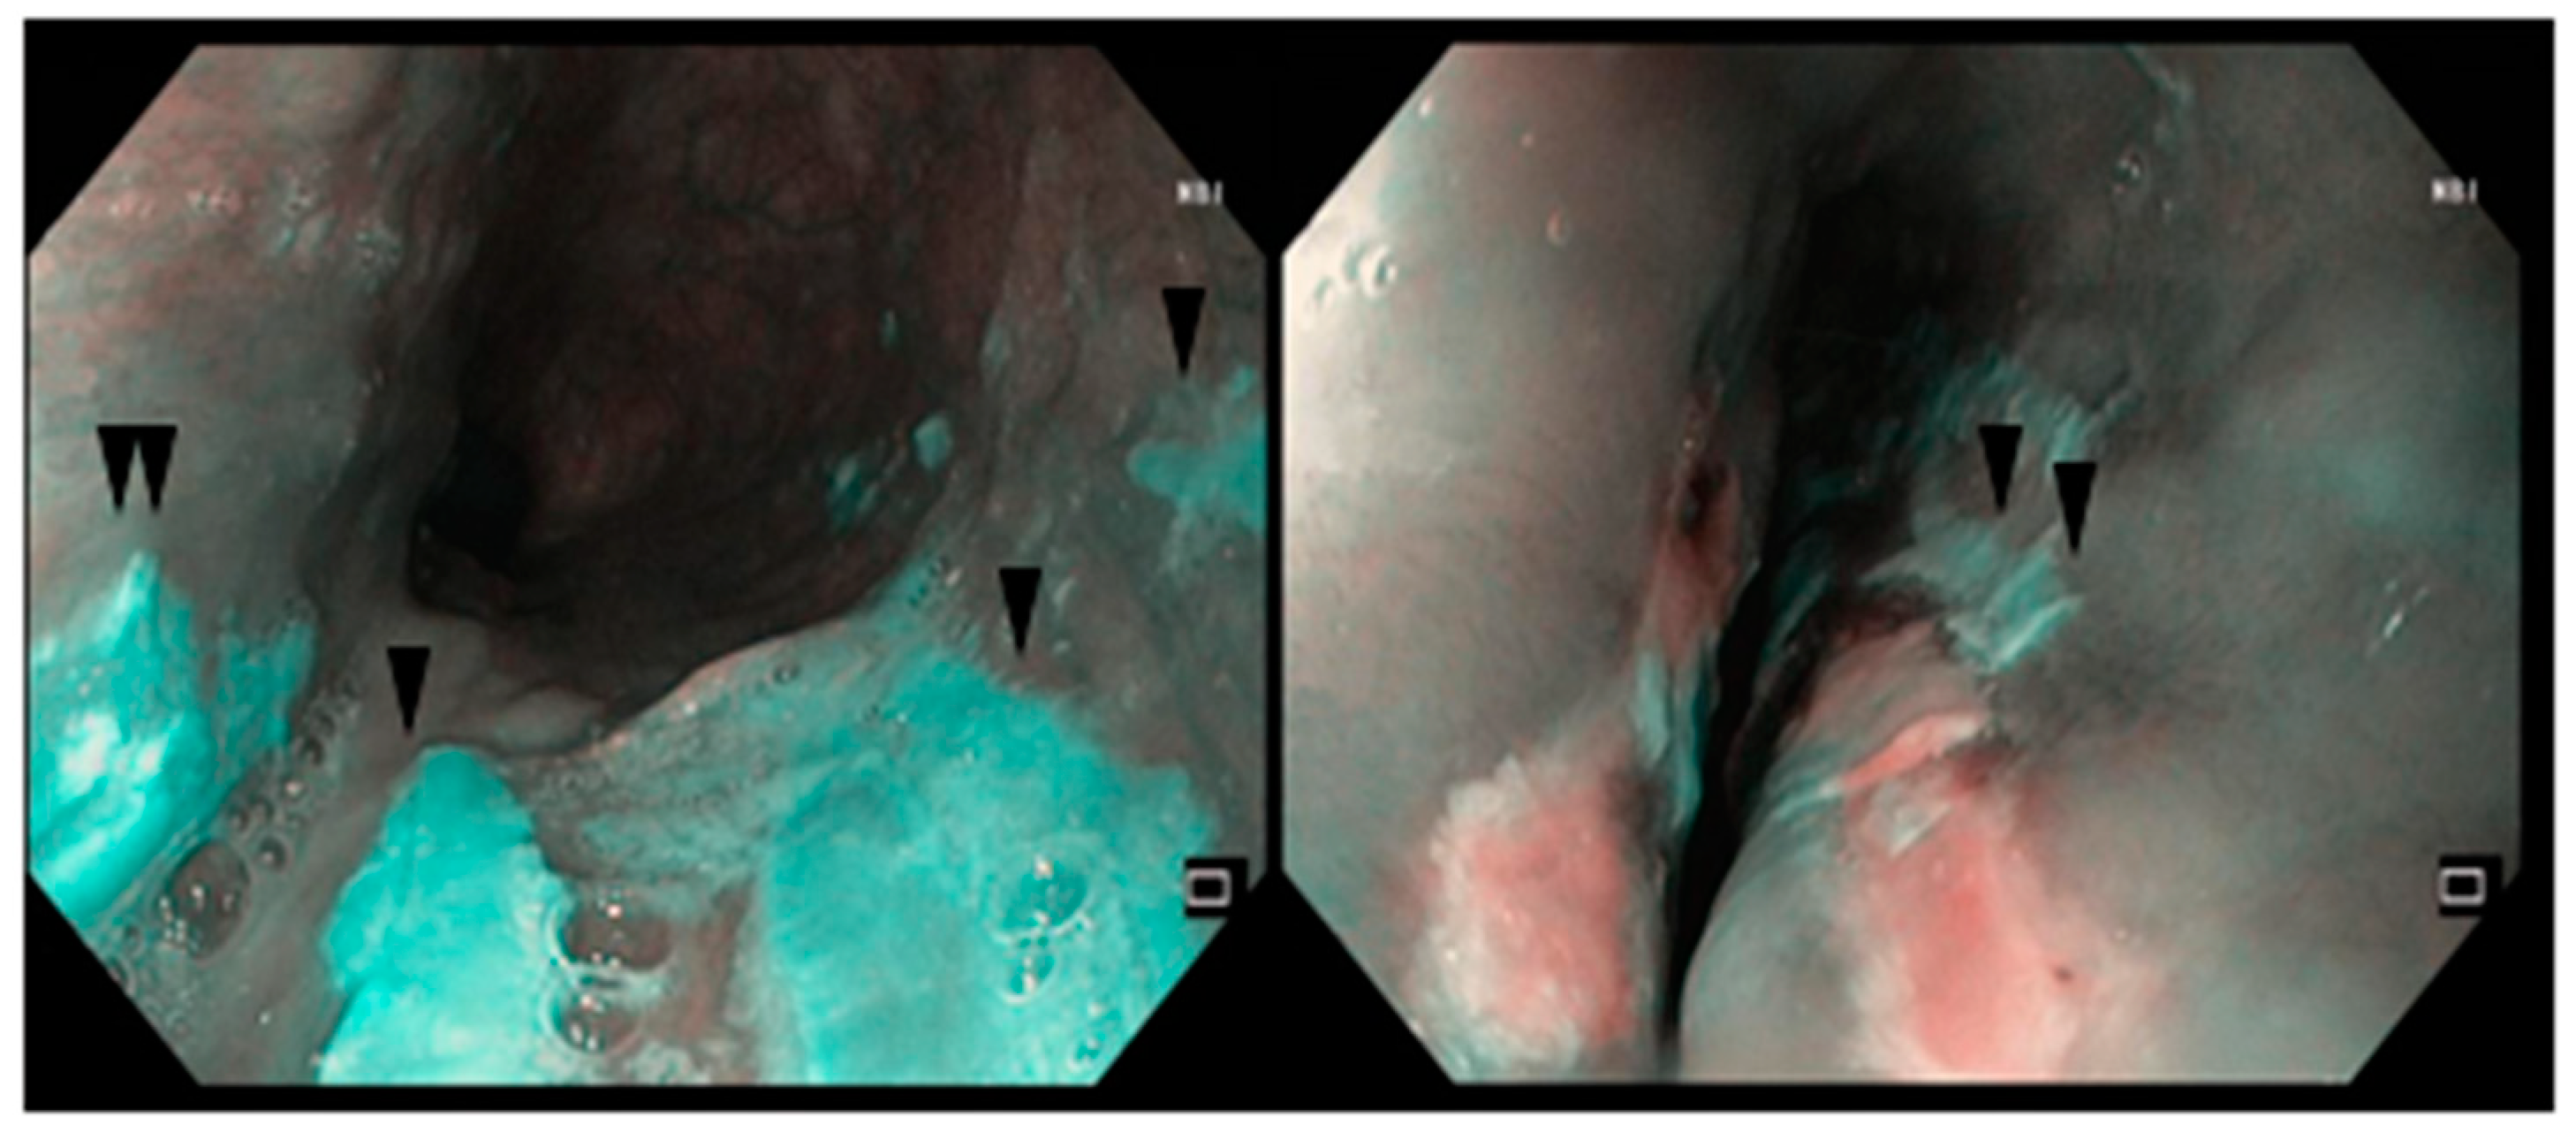

2.1. Case Report #1

2.2. Case Report #2